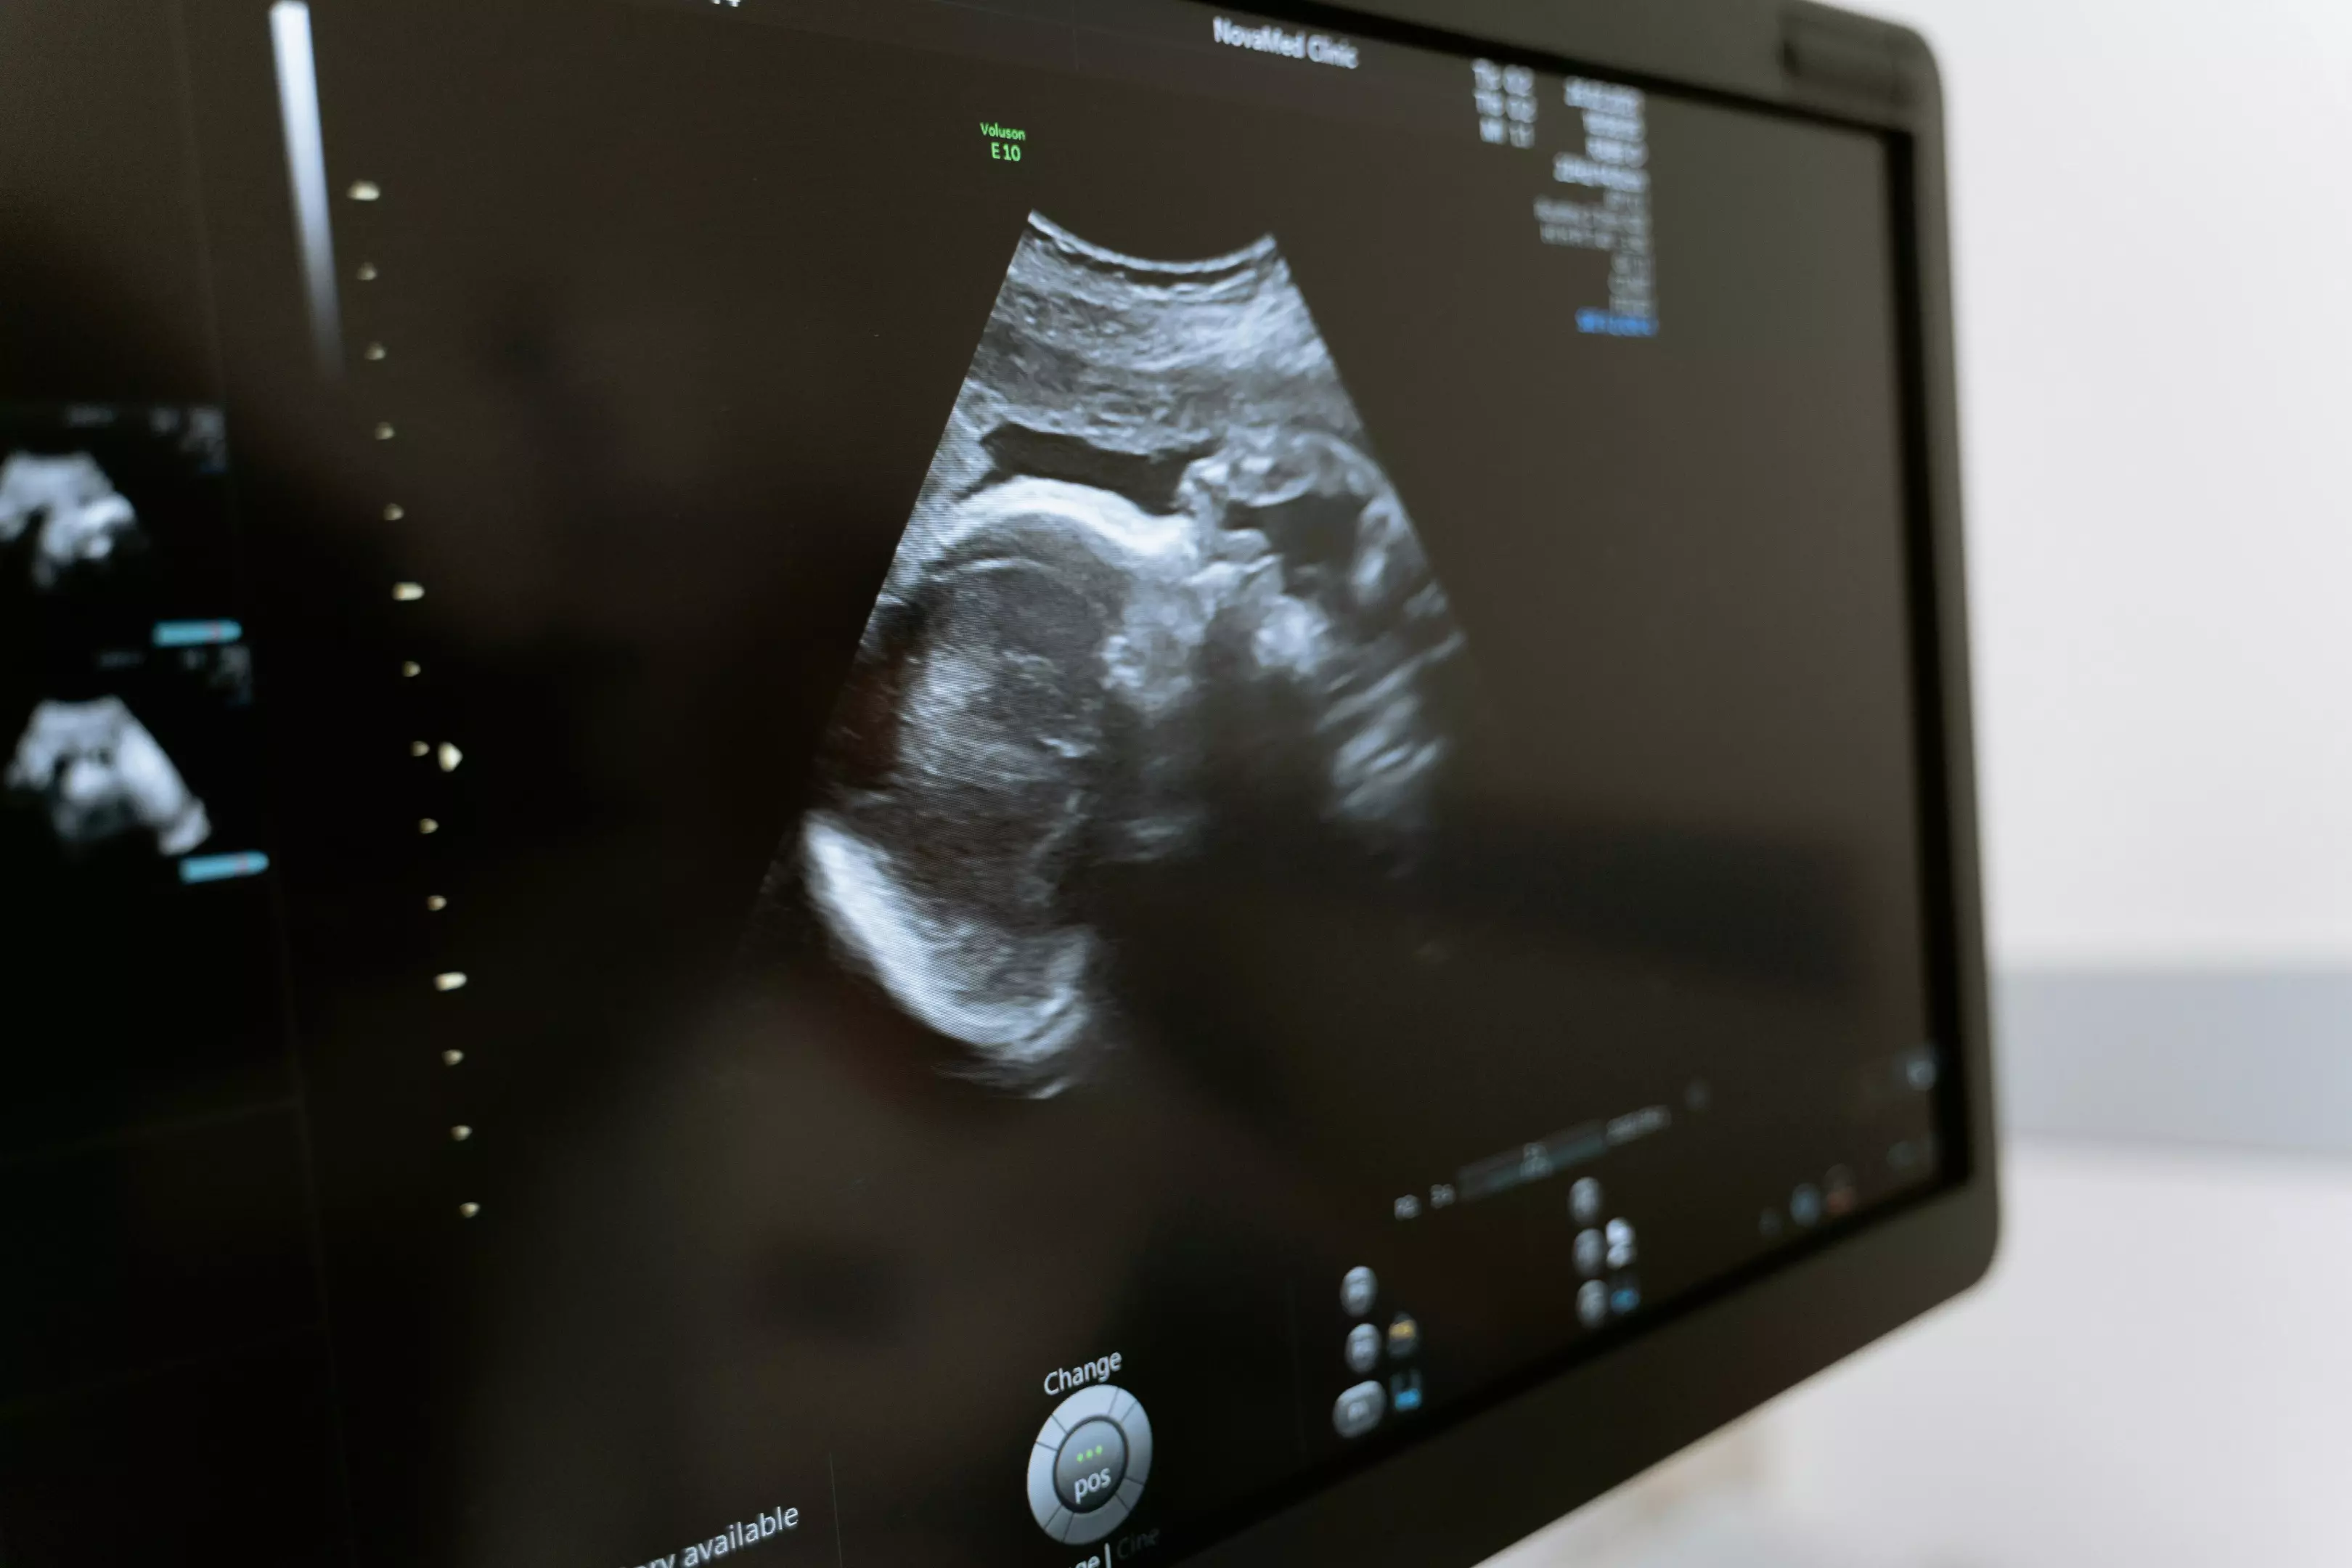

Potrebna vam je precizna i pouzdana dijagnostika? Ordinacija Vitaz osnovana je 2006. godine sa sedištem u Inđiji i već dugi niz godina pruža kvalitetne usluge ultrazvučnih pregleda. Izdvajamo se po dugogodišnjem iskustvu, stručnosti, ljubaznom pristupu i istinskoj brizi o svakom pacijentu.

U okviru naše ordinacije obavljamo širok spektar ultrazvučne dijagnostike, uključujući:

kompletan pregled gornjeg abdomena

ultrazvuk male karlice

pregled mokraćne bešike i prostate

ultrazvuk štitaste žlezde i vrata

pregled mekih tkiva, mišića i zglobova

ultrazvuk dojki i pazušnih jama

pregled skrotuma i testisa

Svi pregledi se obavljaju savremenom opremom, uz stručnu interpretaciju nalaza i maksimalnu pažnju prema pacijentima.

Od ove godine uveli smo i Doppler pregled krvnih sudova, čime smo dodatno proširili obim naših usluga. Na taj način pacijenti mogu obaviti sve potrebne ultrazvučne preglede na jednom mestu, bez potrebe za dodatnim odlascima u druge ustanove.